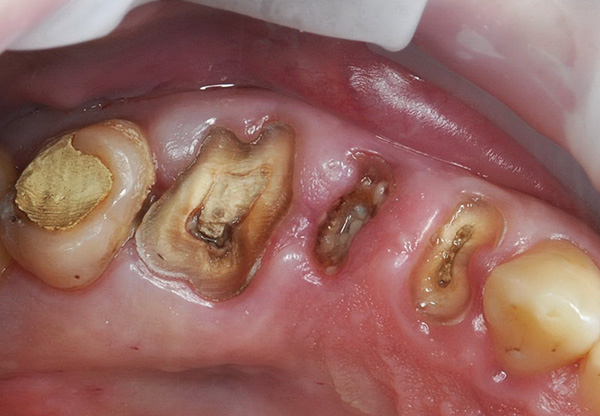

As fotos abaixo demonstram os estágios individuais do método atraumático de remoção de três dentes de uma só vez com um corte preliminar: